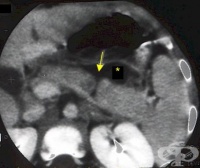

S36.2 Травма на панкреаса

Нараняванията на панкреаса са сравнително редки поради дълбокото му анатомично разположение в ретроп...